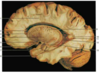

Label 5, 6 & 7

1 - superior temporal gyrus;

2 - inferior frontal gyrus; 3 - insular cortex;

4 - temporal stem;

5 - internal capsule;

6 - thalamus;

7 - lentiform nucleus (the internal and external globus pallidus and the putamen)

8 - frontal horn;

9 - superior circular sulcus;

10 - inferior circular sulcus.

1 - superior temporal gyrus; 2 - inferior frontal gyrus; 3 - insular cortex; 4 - temporal stem; **5 - internal capsule;** **6 - thalamus;** **7 - lentiform nucleus** (the internal and external globus pallidus and the putamen) 8 - frontal horn; 9 - superior circular sulcus; 10 - inferior circular sulcus.